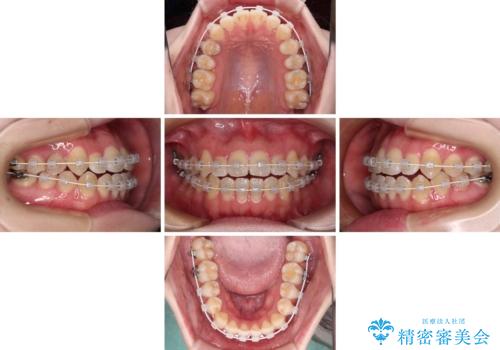

- 審美装置

- 治療期間

- 1年6ヶ月

ワイヤー矯正での開咬改善には時間がかかります。

舌の突出癖改善のトレーニングをしっかりと行っていただき、上下前歯が接触する咬み合わせを達成することができました。